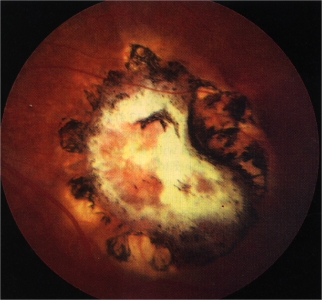

Retinoblastoma

Toxoplasmosis